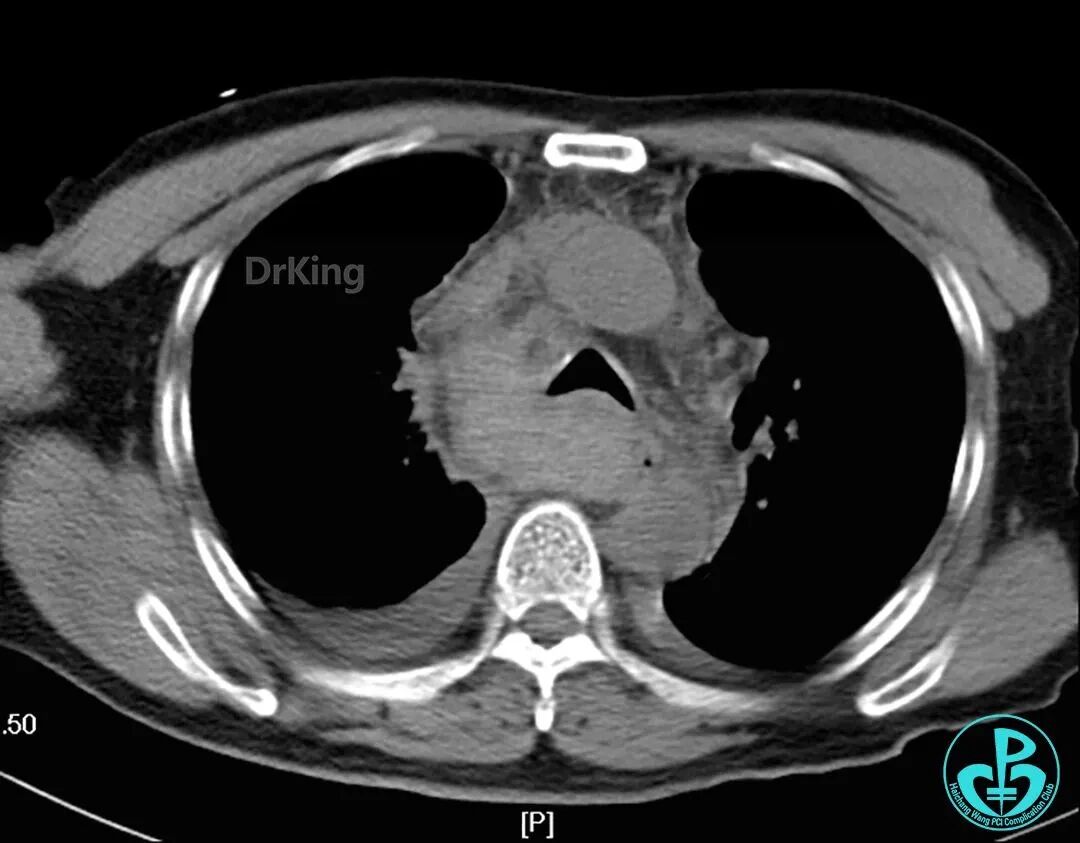

入院前急诊肺CT与术后2小时胸部CT对照,术后发生纵隔血肿。

主动脉弓层面前后CT对照。